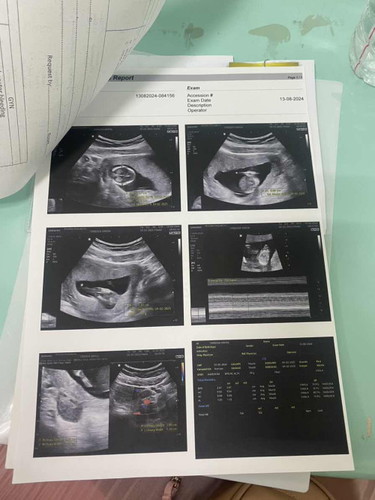

จากโพสที่แล้ว4Wเราไม่เจอน้อง โพสนี้เราเจอน้องเจอหัวใจ มีเสียงหัวใจและคลื่นหัวใจชัดเจนแล้วนะคะ แต่เรามีเลือดออกคุณหมอเลยฉีดยากันแท้งให้เมื่อวาน พอเช้าวันนี้ก็ยังมีเลือดออกอีกจะอันตรายไหมคะ ป้าหมอไม่ได้พูดถึงเลือดออกเลย เลยไม่แน่ใจว่าอันตรายรึเปล่า #ขอบคุณล่วงหน้าสำหรับความคิดเห็นค่ะ #ท้องแรก #ขอความคิดเห็นของคุณแม่หน่อยค่ะ